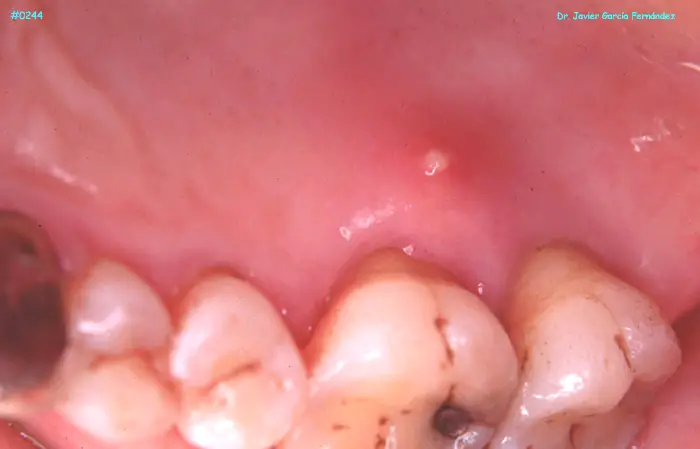

ATLAS DE CIRUGIA PERIODONTAL